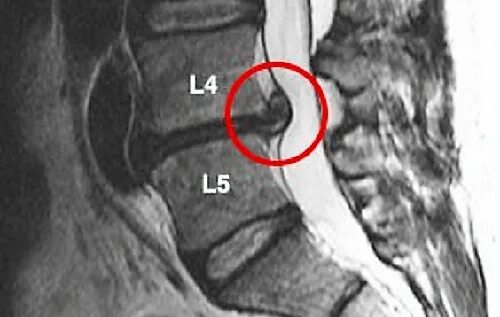

Грыжа диска l4 l5